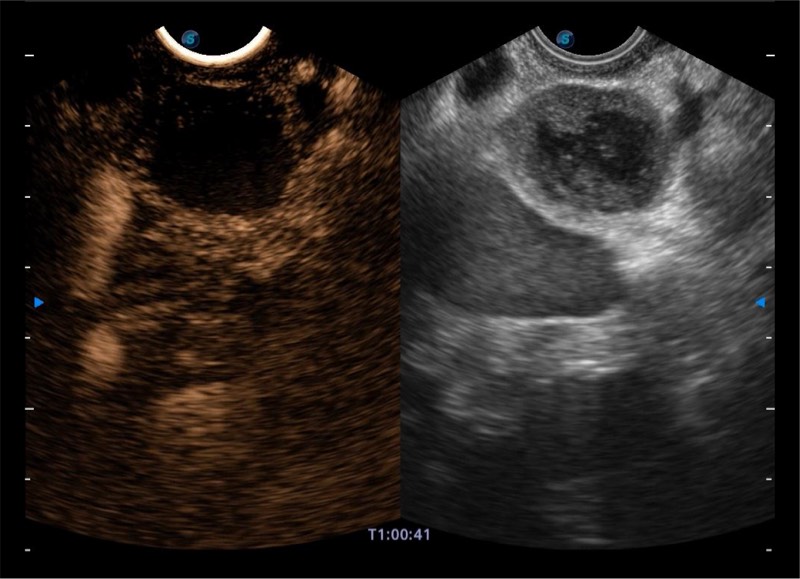

基于二十年的超声技术积累,16877太阳集团提供了最新一代的独立超声主机,在提供高质量图像的同时满足多学科使用。具备常见多普勒技术并提供弹性成像、声学造影等高端影像技术。新一代传感器具有更强的抗干扰能力并减少图像伪影。